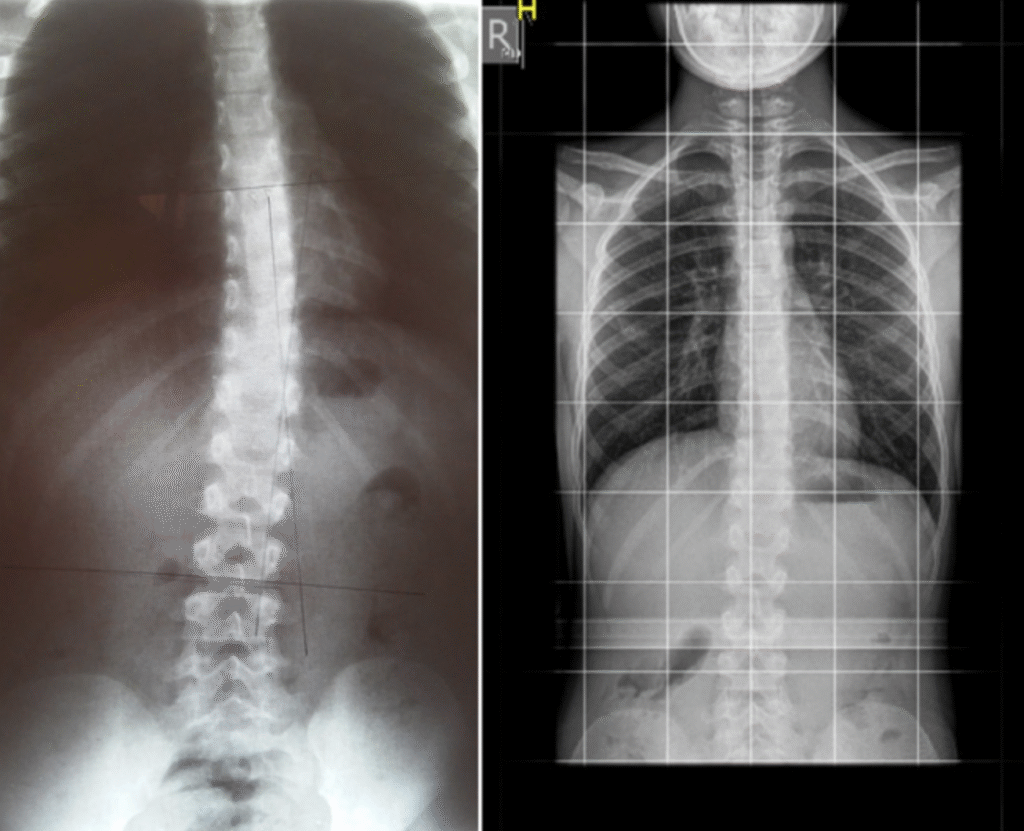

Martyna – 10 lat

Terapia prowadzona w okresie 03.10.2016 – 02.01.2017 (20 zabiegów) Częstotliwość zajęć – 2 x tydz. Po skończonej terapii dziecko było pod kontrolą naszego ośrodka. W lutym 2019 zrobiono zdjęcie RTG, które nie wykazało skrzywienia kręgosłupa.